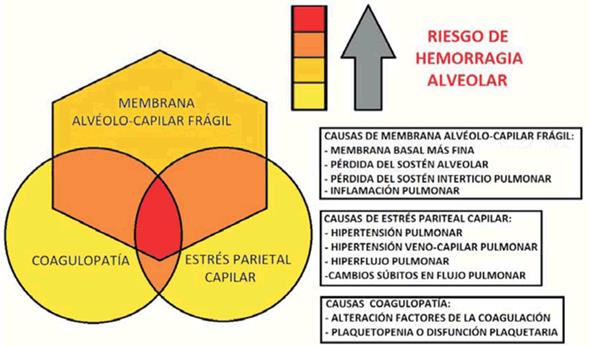

En la (Figura 3) se presenta un esquema que representa la interacción de los distintos factores que pueden incidir en el sangrado alveolar. Se destaca la importancia de la membrana alveolo capilar y la presencia de fragilidad de la misma lo que incrementa el riesgo de falla por estrés y eventual sangrado. A su vez la presencia de estrés parietal capilar y/o alteración en la cascada de la coagulación pueden ser determinantes en el desarrollo de la patología. Estos factores pueden incidir en el desarrollo de HAD incluso en pulmones sanos, ya sean afectados en forma aislada o combinados.

Figura 3: Esquema propuesto para sangrado pulmonar alveolar no inmune. Diagrama de Venn-Euler donde se esquematiza la importancia de la membrana alvéolo-capilar frágil así como la interacción de los factores desarrollados en el texto.